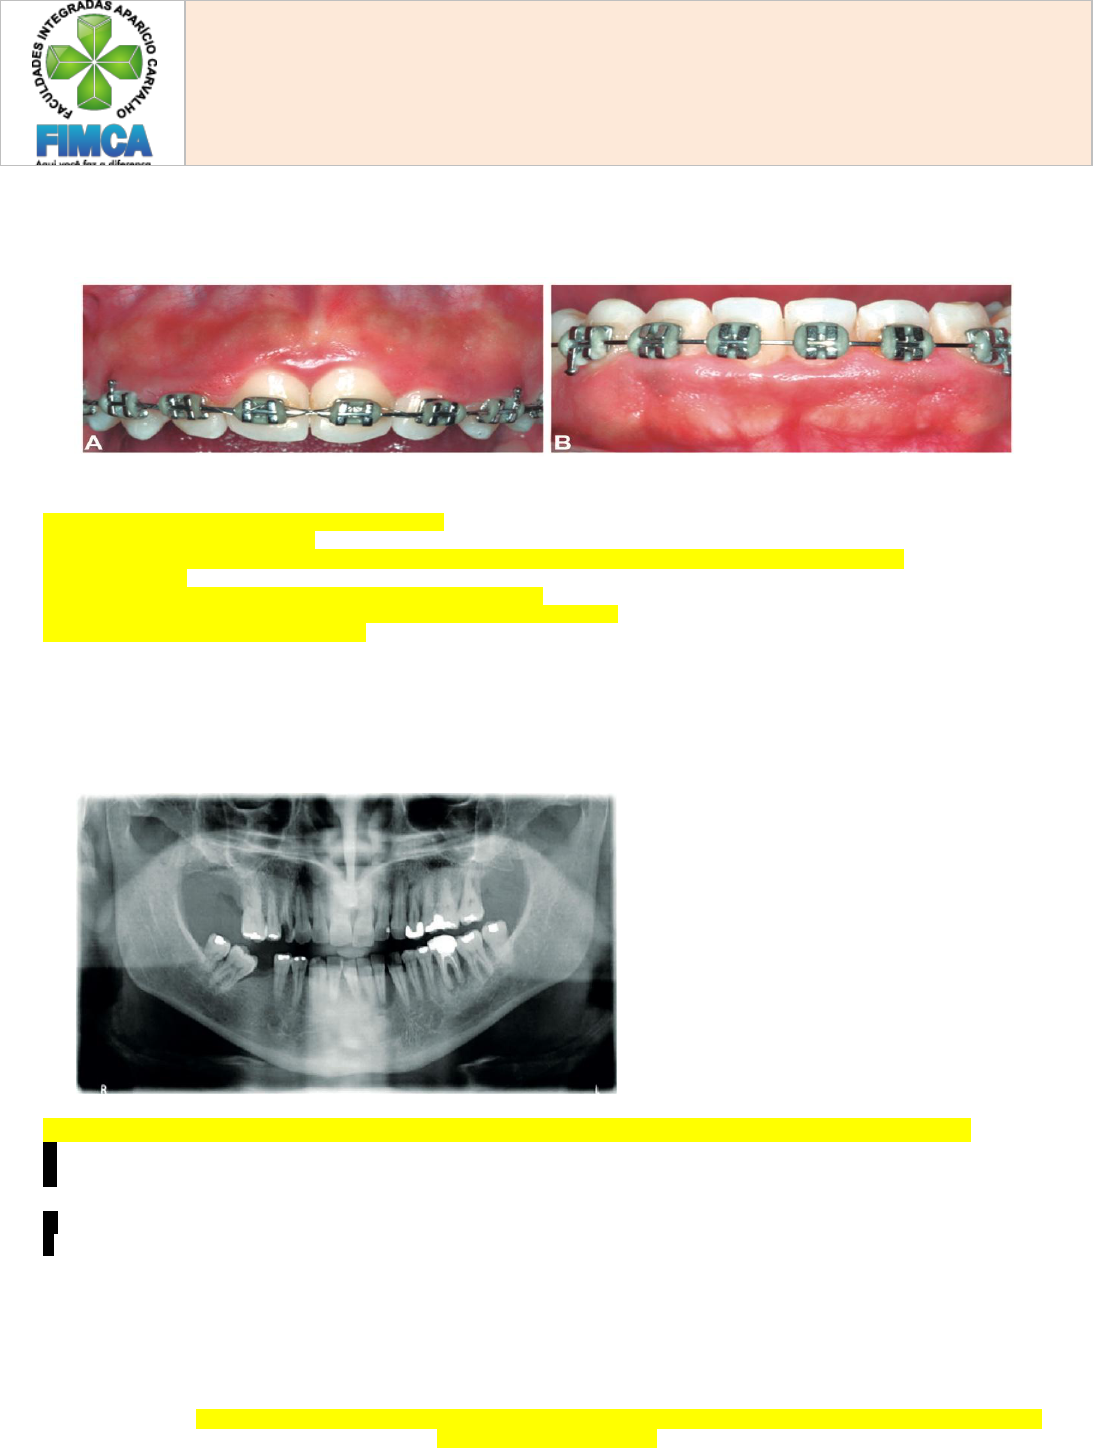

Item 1 - O acúmulo de biofilme em torno do aparelho ortodôntico pode resultar em atividade de cárie e em aumento gengival inflamatório crônico. Um paciente adolescente em tratamento ortodôntico com aparelho fixo apresenta gengiva edemaciada, com coloração vermelha intensa, frouxa e com tendência a sangramento espontâneo (Figuras A e B).

Considerando que o paciente também apresenta manchas brancas ativas de cárie dental sem cavitação, descreva cinco condutas clínicas do cirurgião-dentista adequadas para o tratamento desse paciente.

Item 2 - Paciente de 43 anos de idade, do sexo masculino, relatou, em atendimento odontológico, sangramento na gengiva e quebra de uma restauração na região superior direita. Relatou ser diabético controlado. Ao exame físico, verificam-se fratura coronária no dente 14, sobrecontorno na restauração do dente 24, sangramento generalizado à sondagem, bolsas periodontais no dente 36 com 9 mm de profundidade e envolvimento de furca e, no dente 32, com 8 mm de profundidade de sondagem na distal e vitalidade pulpar positiva.

Considerando-se o quadro clínico e a imagem da radiografia panorâmica acima, a conduta inicial adequada é: